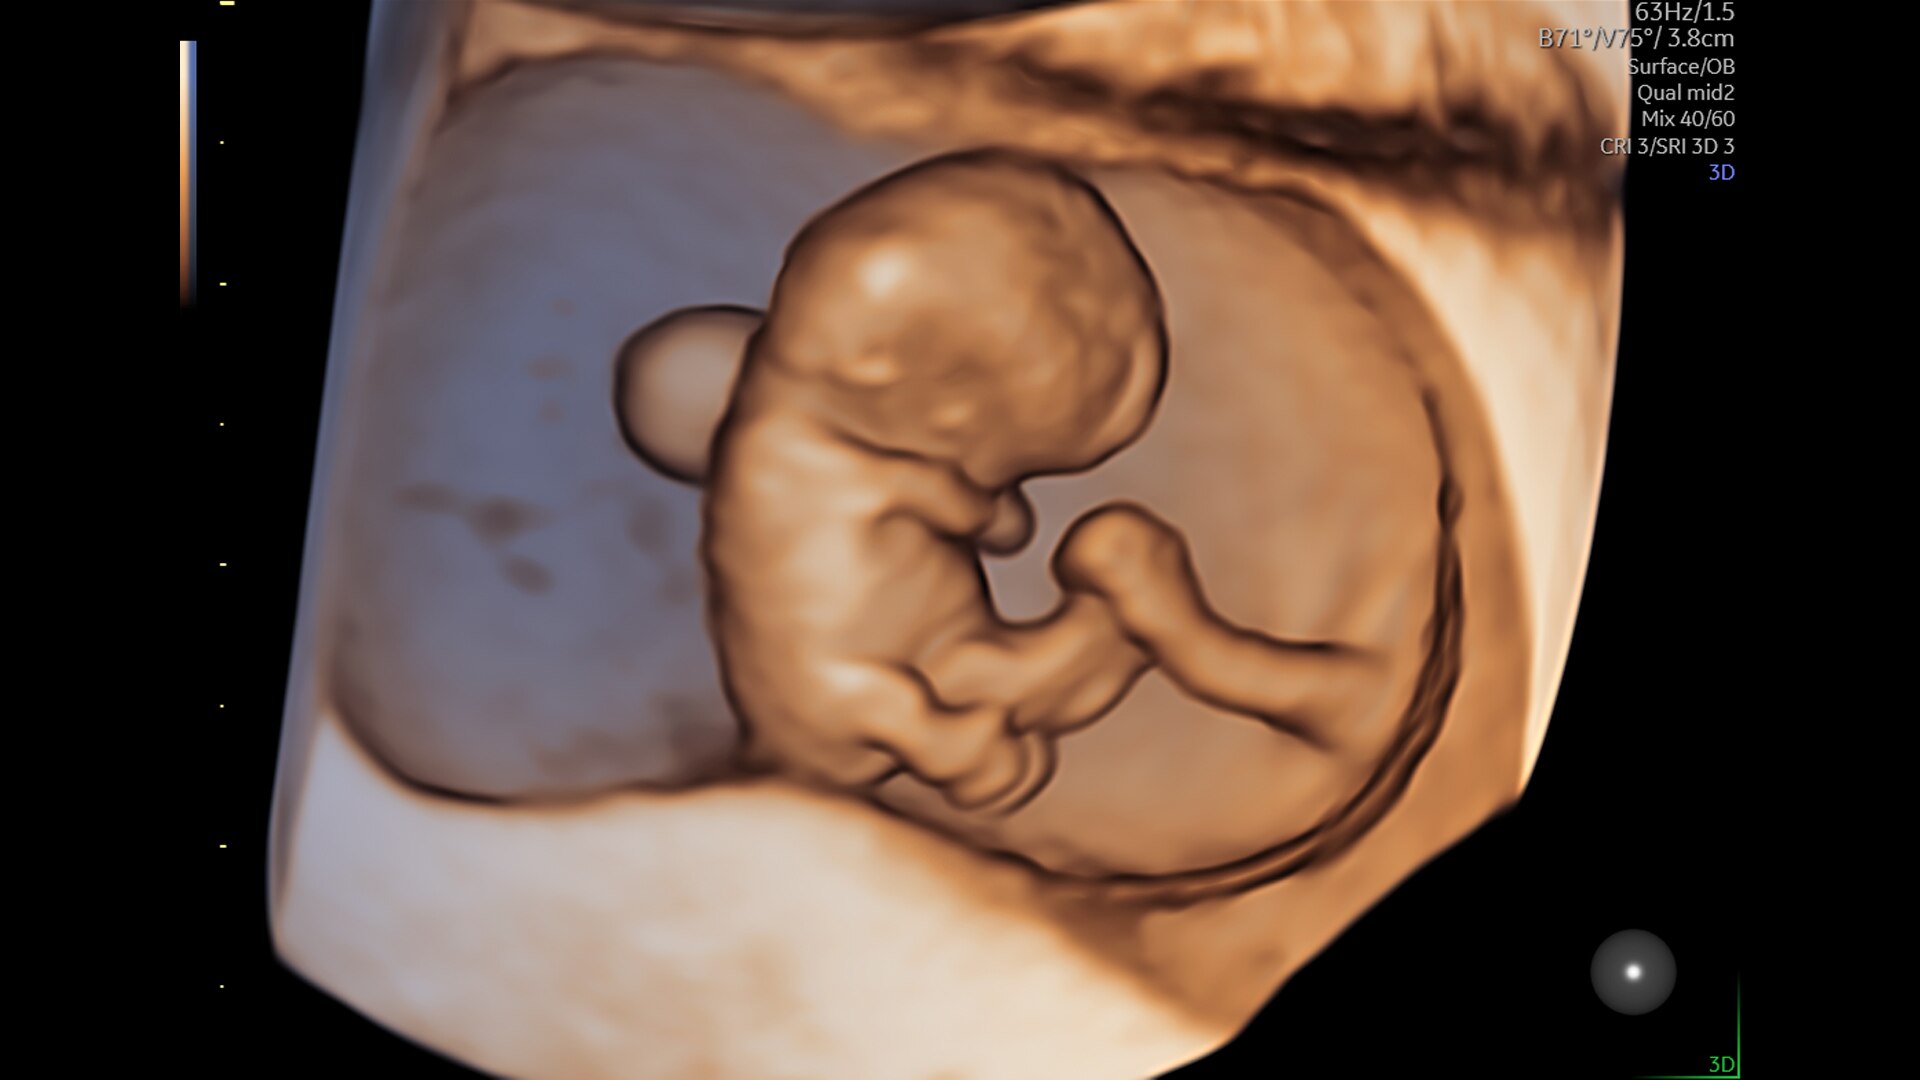

Advanced beamforming capabilities work in harmony with expert-level probes to deliver faster processing speeds and frame rates for enhanced detail and contrast resolution, greater color quality and sensitivity, and exceptional 3D/4D.

SonoLyst

SonoLyst* reduces the time to complete the standard ISUOG 2nd trimester exam requirements by 40%. And with SonoLyst live, it means no more stopping to freeze, annotate, or store.